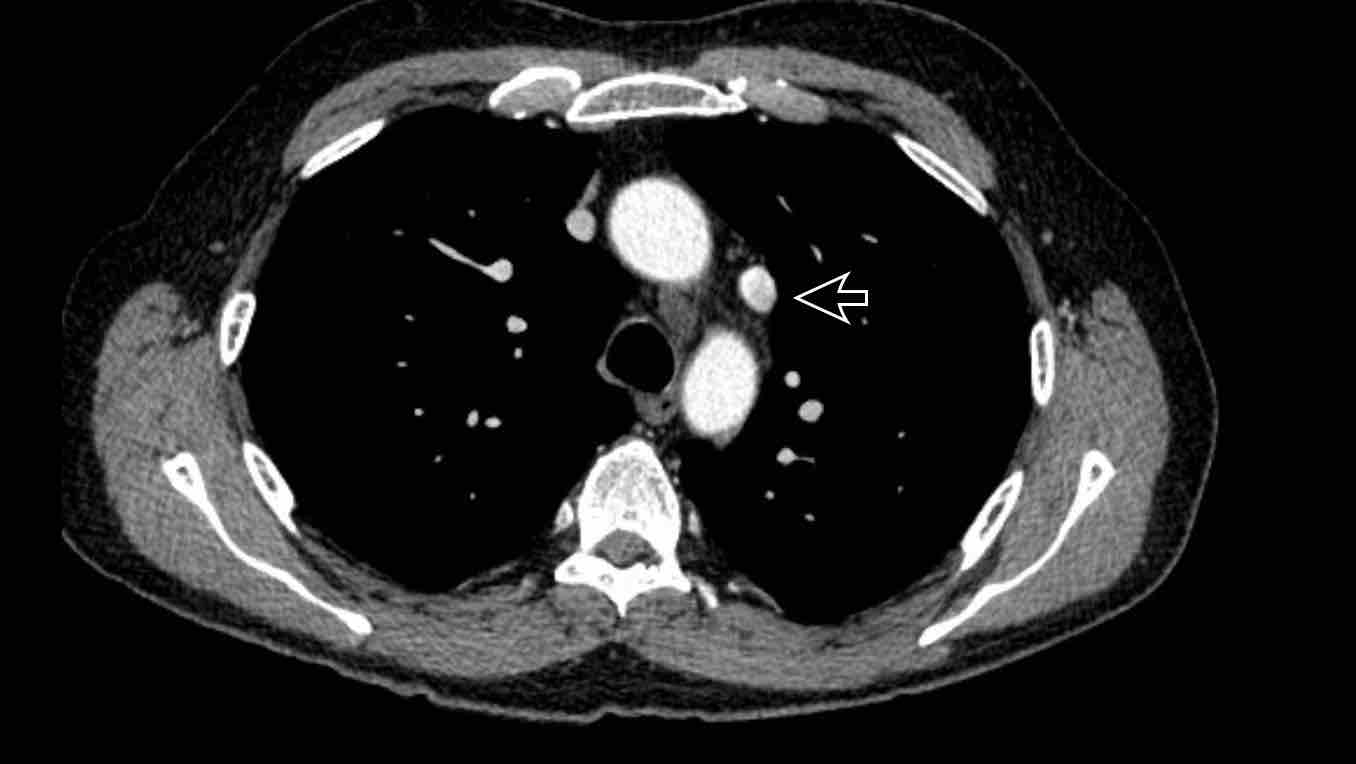

Hình ảnh

Bệnh nhân này được lên kế hoạch cắt thùy trên phải do ung thư phổi và bất thường mạch máu này ban đầu đã bị bỏ sót trên hình ảnh CT.

Những hệ quả trong phẫu thuật của bất thường như vậy nhấn mạnh tầm quan trọng của việc không bỏ sót các biến thể này.

Cuộn qua các hình ảnh.

PAPVR bên trái phát hiện tình cờ với dẫn lưu trên tim của máu từ thùy trên trái vào tĩnh mạch tay đầu trái (các mũi tên).